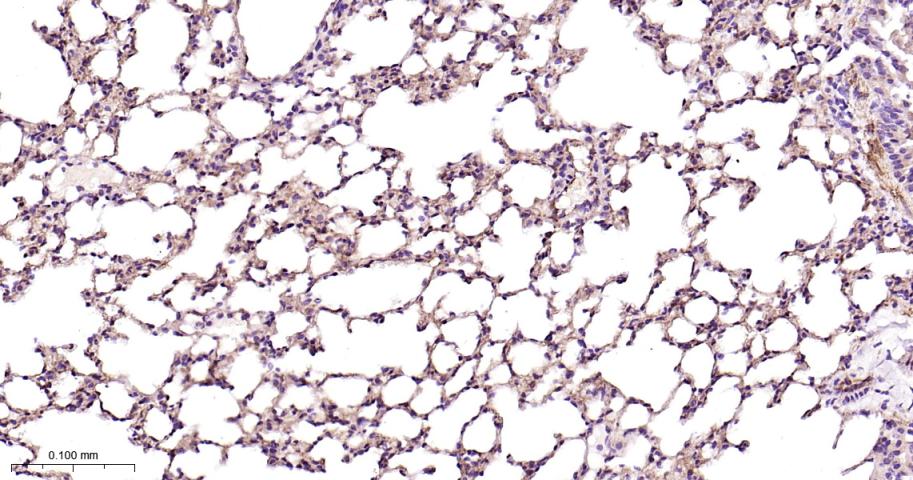

Paraformaldehyde-fixed, paraffin embedded Rat Lung; Antigen retrieval by boiling in sodium citrate buffer (pH6.0) for 15 min; Antibody incubation with CD146 Monoclonal Antibody, Unconjugated(bsm-61136R) at 1:200 overnight at 4°C, followed by conjugation to the bs-0295G-HRP and DAB (C-0010) staining.

Paraformaldehyde-fixed, paraffin embedded Mouse Lung; Antigen retrieval by boiling in sodium citrate buffer (pH6.0) for 15 min; Antibody incubation with CD146 Monoclonal Antibody, Unconjugated(bsm-61136R) at 1:200 overnight at 4°C, followed by conjugation to the bs-0295G-HRP and DAB (C-0010) staining.